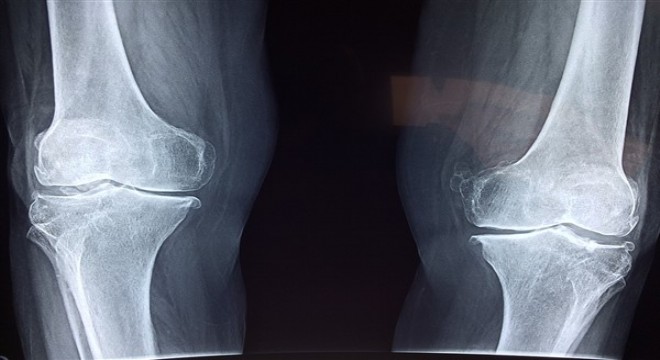

Farklı nedenlerden dolayı kırılan kemiklerde kaynamanın gecikmesi veya kaynamanın olmaması, yaş, cinsiyet, beslenme ve yaşam biçimi gibi birçok etkene bağlı olarak gerçekleşiyor.

Farklı nedenlerden dolayı kırılan kemiklerde kaynamanın gecikmesi veya kaynamanın olmaması, yaş, cinsiyet, beslenme ve yaşam biçimi gibi birçok etkene bağlı olarak gerçekleşiyor. Sigara kullanımının kemik kaynamasını geciktirdiğini vurgulayan uzmanlar, beslenme ve şeker hastalığı gibi faktörlerin de kaynamanın gecikmesinde etkili olduğuna dikkat çekiyor. Uzmanlar, kemik sağlığı için D vitamini açısından zengin olan güneş ışınları ile kalsiyum ve protein açısından zengin yiyeceklerden faydalanılmasını öneriyor.

Sigara kırılan kemiğin kaynamasını geciktiriyor

Canbora, beslenme, şeker hastalığı ve sigara bağımlılığının kaynamayı geciktirdiğine dikkat çekti ve sözlerini şöyle sürdürdü:

“Kırığın kaynamasında makrofajlar, birtakım uygulanan kimyasal mediatörler gibi çok önemli faktörler var ve sigara bunların hepsini baskılıyor. Sigara bağımlılığında kemik kaynaması geciktiği kanıtlanmış. Ayrıca kaynamamanın da önemli bir sebebi sigara diyebiliriz. Kırık kaynaması çok karmaşık bir süreç, kaynamasında önemli olan hücreler, kök hücreler var. İçilen her sigara arttıkça nikotin, kemik kaynaması sırasında kök hücrelerin gerekli birtakım aktivasyonlarını engelliyor. Sigara bağımlılığının yanında kemik erimesi, belli yaş üzerinde önemli. Özellikle menapoz sonrası kadınlarda östrojen çekiliyor, osteoporoz da metabolizmayı yavaşlatıyor. Bazen kullanılan bazı ağrı kesiciler bile kaynamayı geciktirebiliyor. Kırıklarla ilgili uzmanların, kullanılan ağrı kesicileri, sigara bağımlılıklarını sorgulamaları ve süreci yönetmeleri gerekiyor.”